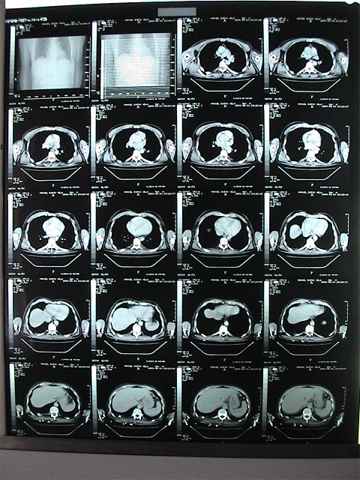

Y además cerciorarnos que el riñón y zonas adyacentes

están preservados, para lo cual de inmediato se le practica TAC lumbar,

Sedimento urinario y radiología de parrilla costal.

Tac negativo